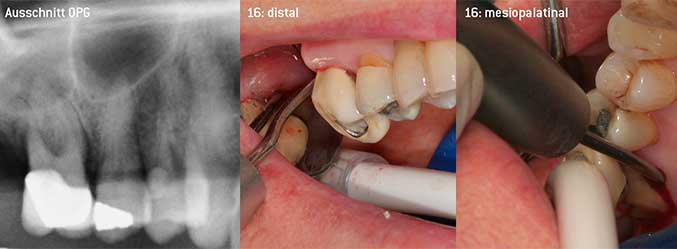

Als Initiatoren zur Entwicklung der neuen diamantierten Luftscaler-Spitze 3AP sahen es beide Zahnärzte als notwendig an, die Einschränkung in der Handhabung bisher kommerziell vermarkteter diamantierter Spitzen insbesondere während der Furkationstherapie oder in engen Knochentaschen zu verbessern. Dies sollte unabhängig von nicht-chirurgischem (Abbildung 2) oder chirurgischem Vorgehen sein (Abbildung 3).

Offenes Debridement der Furkationen an 16 und 17

Abb. 3: Offenes Debridement der Furkationen an 16 und 17 bei fortgeschrittenem Attachmentverlust